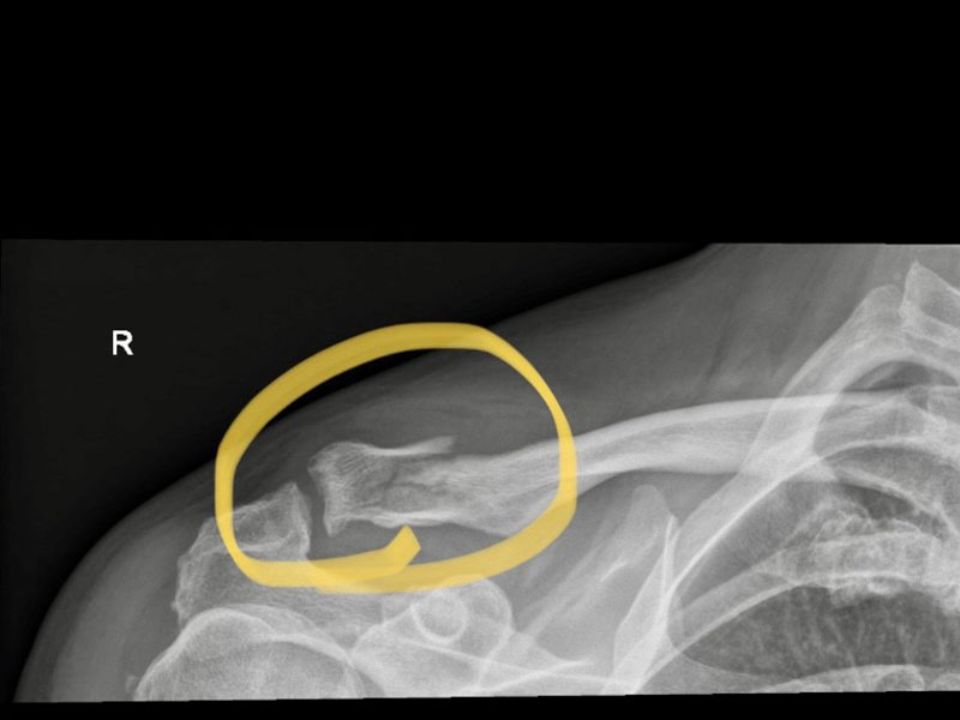

Die Röntgenbilder sorgen für Klarheit: Das rechte Schlüsselbein ist gebrochen, immerhin glatt und sauber, was den Heilungsprozess beschleunigen wird. Dazu kommen eine starke Rippenfraktur und Prellungen am Oberkörper. Flüssigkeit hat sich im Körper jedoch nicht angesammelt, Milz und Leber und Lunge sind nicht betroffen. «Glück im Unglück», meint Dänu.